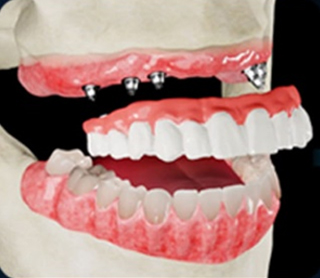

• 임플란트 식립 및

임시치아 장착

• 풀아치 임플란트

최종보철물 장착